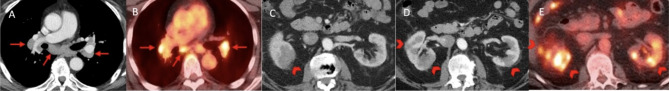

Case presentation: A 71-year-old male with malignant melanoma (BRAF wild-type) initially received one cycle of adjuvant pembrolizumab, followed by four cycles of ipilimumab/nivolumab after the occurrence of lung metastases. Four months later, a follow-up computed tomography (CT) revealed infiltrative masses in the kidneys, along with abnormal mediastinal and hilar lymphadenopathy but his baseline serum creatinine remained stable. A subsequent kidney biopsy showed renal parenchyma with significant interstitial nephritis and an increase in IgG4-positive plasma cells, with no evidence of malignancy. Plasma IgG4 levels were elevated at 294 mg/dL (normal 11-157 mg/dL), and complement C4 level was low at < 8 mg/dL. In addition, the patient had an asymptomatic rise in lipase (105 U/L, normal 7-60 U/L), but had no other findings to suggest pancreatitis. The patient was started on prednisone 40 mg daily with a plan to taper. A follow-up CT scan performed four weeks later showed near-complete resolution of the previously observed mediastinal lymphadenopathy and bilateral infiltrative renal masses.